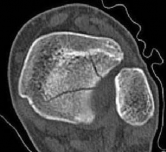

Standard orthogonal radiographs (anteroposterior and lateral) are insufficient for evaluating tibial fractures with suspected plafond extension. A dedicated computed tomography (CT) scan of the ankle with coronal, sagittal, and 3D reconstructions is mandatory.

Image

The CT scan serves several critical functions. First, it identifies the exact location and orientation of the articular split. Second, it dictates the trajectory of the independent articular lag screws, ensuring they are placed perfectly perpendicular to the fracture plane. Third, and perhaps most importantly, it allows the surgeon to map the safe zones for these lag screws so they do not obstruct the planned path of the intramedullary nail.